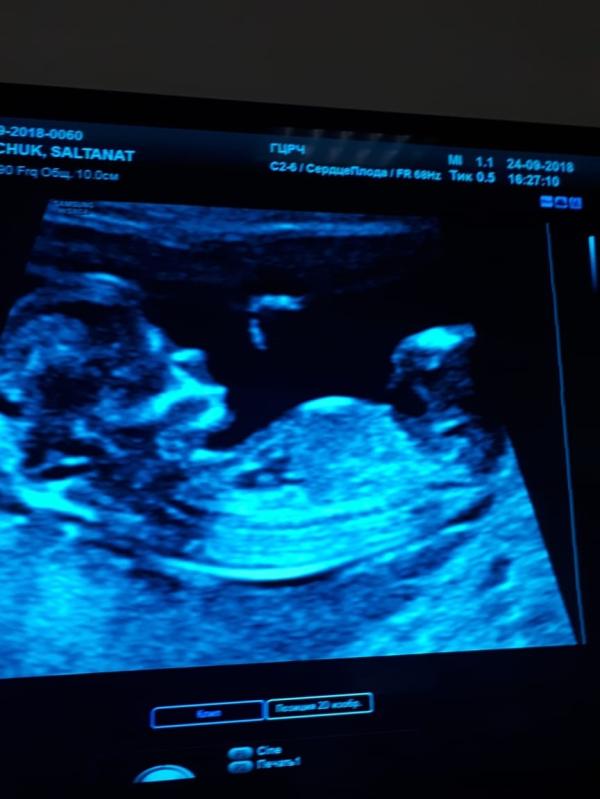

«Мозги на месте, сердце нормально, кишки на месте, глаза где надо, руки ноги пальчики, все есть...»

«Пол не видно, предположительно девочка»

Капец узист. В 5а кабинете какойто молодой парень. Снимок не дали, закончилось...🤷🏻♀️ смотрел мало, нечётко. Бахтияр Утегенов что ли... чет такое.

Еще говорит, сердцебиение слушать не будем, так как от нагрузки оно у малыша может остановиться. 🤷🏻♀️🤷🏻♀️🤷🏻♀️ хочется разозлиться. Но я же добрая...

Не понравилось мне в гцрч. Не пойду я больше туда. Что с дочей ходила...